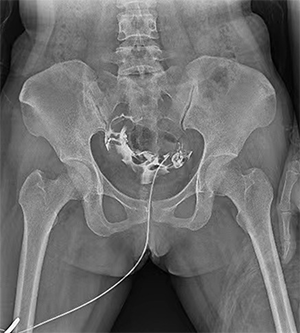

PLD6500系列是普利德研發(fā)的醫(yī)用數(shù)字X線攝影機,采用雙立柱結構,可供各級醫(yī)院放射科對頭部、胸部、腹部、腰椎、四肢等部位進行立位、臥位、正位、側位的數(shù)字攝影檢查。

無需患者移動即可完成對全身各部位的檢查。